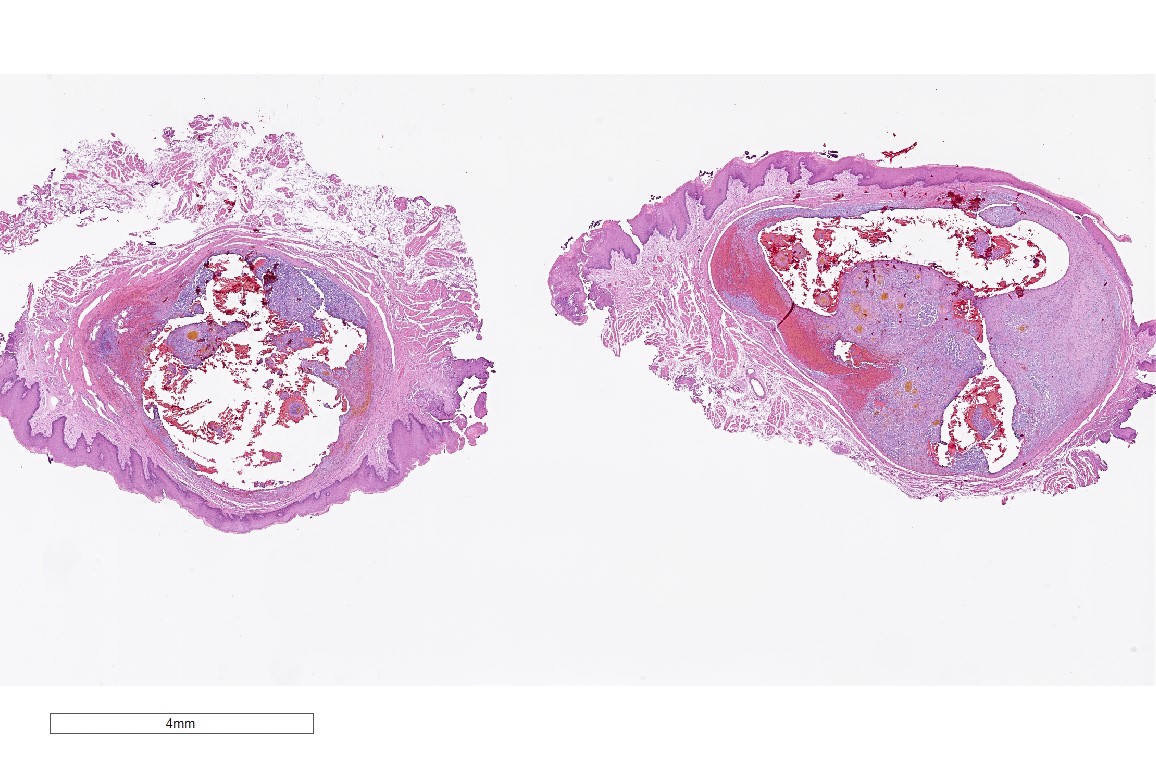

Microscopic (histologic) images